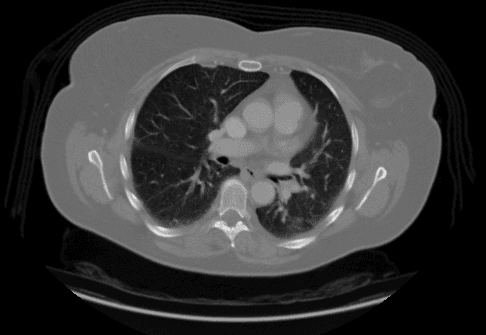

Sample image of chest CT scan that

has Adenocarcinoma lung cancer.